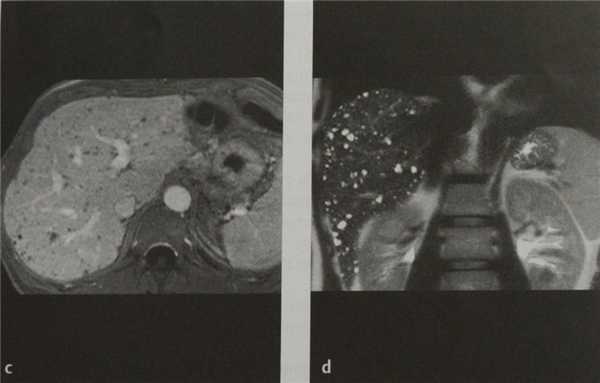

(Правый) Цветовая допплерография подтверждает, что у этого пациента с множественными гамартомами печени отсутствует васкуляризация их кистозного содержимого. (Левый) КТ с контрастированием у этого же пациента, аксиальная проекция. Визуализируются множественные крошечные гамартомы печени низкой плотности, хаотично расположенные по всей паренхиме печени.

(Правый) МРТ печени, Т2 FS, аксиальная проекция. Визуализируются многочисленные очаги сигнала высокой интенсивности, представляющие собой гамартомы печени.

(Слева) На аксиальной Т2 ВИ МР томограмме визуализируются мелкие, гиперинтенсивные билиарные гамартомы. Печень у этого пациента увеличена в размерах, нарушена ее морфология. Визуализируются также добавочные и увеличенные печеночные артерии - признак врожденного фиброза печени.

(Справа) На Т2 ВИ МР томограмме у этого же пациента визуализируются более крупные кистозные образования, сообщающиеся с билиарным трактом и представляющие собой кисты аберрантных желчных протоков (проявление болезни Кароли).

a) УЗИ. Негомогенное изображение с мелкими трудноопределяемыми гипоэхогенными очагами.

b) КТ после введения контраста. Множественные мелкие очаги пониженной плотности, не накапливающие контраст.

c) МРТ после введения контраста. Множественные мелкие гипоинтенсивные очаги, не накапливающие контраст.

d) МР-изображение в режиме НАSТЕ. Множественные гиперинтенсивные очаги с кистозным компонентом.